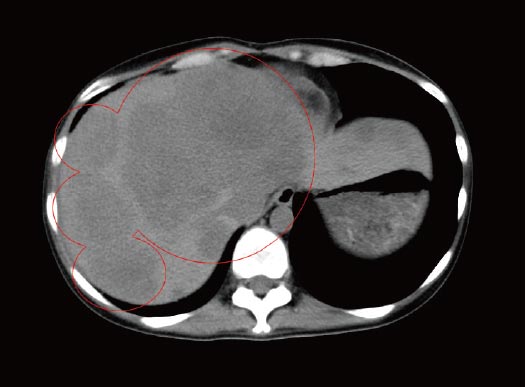

治療前のCT検査結果

来院時のCT(下の画像)では肝臓の右葉に大きく広がる肝転移病巣が認められました。両像所見から勘案すると、正常に機能している肝臓部分は20%以下と推測され、肝不全による病状の急変も非常に懸念される症例でした。